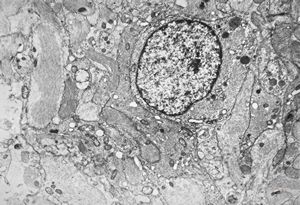

M,10y. | herpetic encephalitis